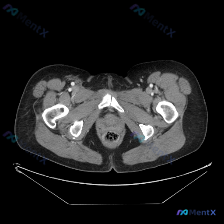

今天看到一个很有意思的资料,虽然不是典型的“疑难病例”,但特别考验临床思维的基本功,整理一下和大家分享。 --- 先看“问题”与“资料” - 临床指向:询问“脾脏病变” - 提供影像:盆腔CT横断面(软组织窗) 影像所见(严格基于提供的层面) 这张图的解剖还是很清楚的: 1. 盆腔脏器:直肠管壁光整...